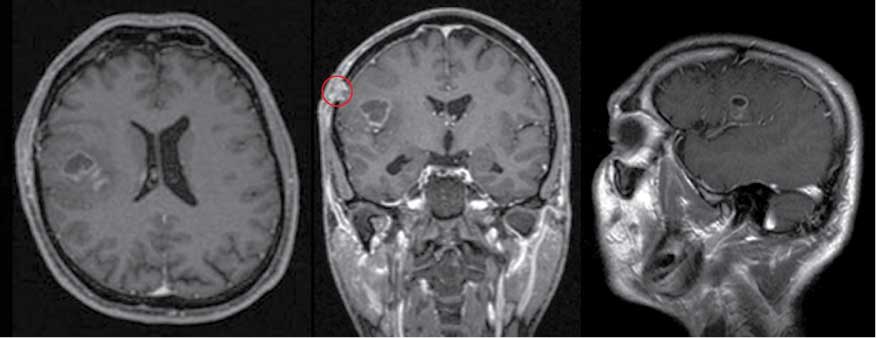

One of the patients treated in this study was a 44-year-old right handed male patient (Table 1, number 2) with a left fronto-lateral glioblastoma. The initial symptoms were a sudden speech arrest followed by a generalized seizure which occurred after the patient went for a sauna 4 weeks before being admitted to our department. After being brought to a hospital the initial cranial computed tomography (CT) showed a right fronto-lateral lesion. An MRI was then performed showing a lesion suspicious of a glioblastoma. A biopsy was performed at another institution confirming the diagnosis of a glioblastoma. After being admitted to our institution for further treatment, the patient underwent thorough preoperative imaging which included T1, 3D MP-RAGE MRI with contrast enhancement (Figure 1), T2 sequences, DTI as well as BOLD functional MRI scans. Functional neuroradiological imaging confirmed the lateralization of the language mainly on the right side next to the contrast enhancing lesion (Figure 1). Based on this finding, it was decided that an awake craniotomy was the best strategy to preserve the language function. The patient gave his written informed consent for an awake surgery in the CAC protocol. Before surgery the neuropsychologist performed several tests that were selected from a range of available standardized tests adapted for German speaking people. The same test battery was then also used for the intra-, and postoperative assessment.

Preoperative magnetic resonance imaging (MRI) showing the right fronto-lateral glioblastoma and the scar tissue (red circle) from the previously performed biopsy. The fMRI image on the far left shows the main lateralization of the language function on the right side anterior to the lesion.